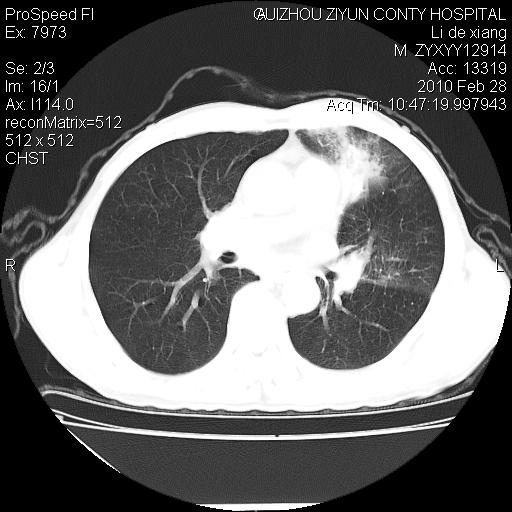

标题: CT24776:男 71Y 咳嗽咳痰胸痛两月,伴声音嘶哑。 [打印本页]

标题: CT24776:男 71Y 咳嗽咳痰胸痛两月,伴声音嘶哑。

左侧中央型肺癌伴左肺上叶阻塞性肺炎及节段性不张可能性大,建议纤支镜检查!

左侧中央型肺癌伴左肺上叶阻塞性肺炎及节段性不张可能性大,建议纤支镜检查!纵隔淋巴结转移.

左肺门部肿块,伴左上肺斑块影,周边模糊,支持左肺中央型肺癌伴节段性不张及阻塞性肺炎,结合支气管镜检查。

左上叶支气管狭窄,阻塞性病变,肺门肿块,纵隔及肺门淋巴结增大,中央性肺癌

左肺中央型肺癌并阻塞性改变、纵膈 淋巴结转移

左侧中央型肺癌伴左肺上叶阻塞性肺炎及纵隔淋巴结转移